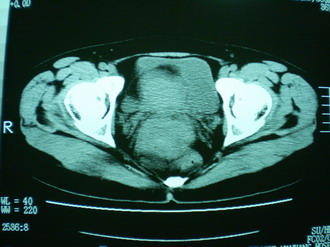

子宫增大,内可见类三角形低密度区,子宫后方可见类圆形团块状影,内部密度不均匀,可见靶样结构,结合病史考虑1子宫后方宫外孕(宫内假孕囊形成)2子宫肌瘤合并妊娠

子宫明显前倾,增大,宫颈增大呈分叶状。子宫直肠窝见不规则形水样低密度。(膀胱胀尿不理想)

考虑:1、宫颈部占位;

2、子宫直肠窝少量积液(盆腔炎所致)。

考虑:1、宫颈部占位(宫颈癌?);

2、子宫直肠窝少量积液。